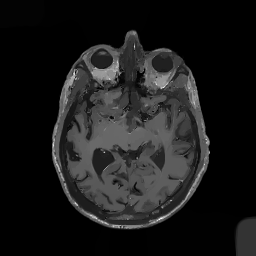

Multi-modality (or multi-channel) imaging is becoming increasingly important and more widely available, e.g. hyperspectral imaging in remote sensing, spectral CT in material sciences as well as multi-contrast MRI and PET-MR in medicine. Research in the last decades resulted in a plethora of mathematical methods to combine data from several modalities. State-of-the-art methods, often formulated as variational regularization, have shown to significantly improve image reconstruction both quantitatively and qualitatively. Almost all of these models rely on the assumption that the modalities are perfectly registered, which is not the case in most real world applications. We propose a variational framework which jointly performs reconstruction and registration, thereby overcoming this hurdle. Numerical results on simulated and real data show the potential of the proposed strategy for various applications in multi-contrast MRI, PET-MR, and hyperspectral imaging: typical misalignments between modalities such as rotations, translations, zooms can be effectively corrected during the reconstruction process. Therefore the proposed framework allows the robust exploitation of shared information across multiple modalities under real conditions.